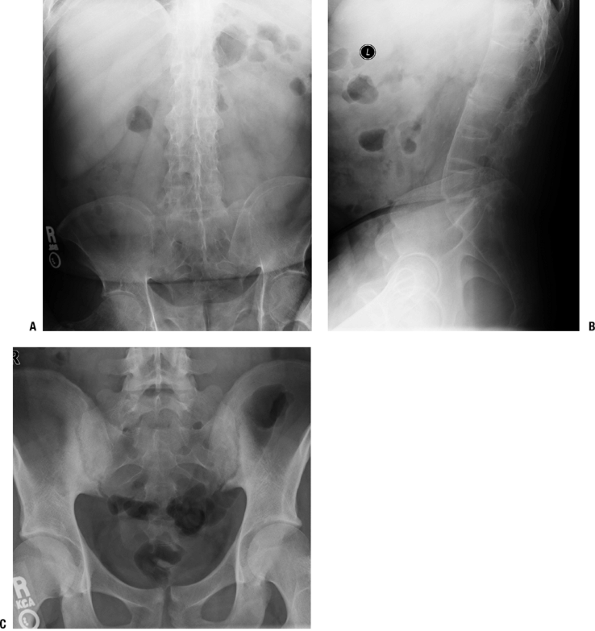

Radiologic Findings (Figs. 21-10 and 21-11)

-

Vertebral bodies have squared margins (marginal erosion) or central cyst suggesting infection.

Syndesmophytes at margins of vertebral

bodies produce “bamboo spine” appearance (ossification of outer layers

of annulus fibrosis); differential diagnosis with diffuse idiopathic

skeletal hyperostosis: lack of ossification of anterior and posterior

longitudinal ligaments in ankylosing spondylitis (see Fig. 21-11) -

Diffuse osteoporosis

Fusion of sacroiliac joints

Erosions and ossification of insertions

of ligaments, tendons, and capsules into bone (spinous processes,

greater trochanters, pelvis, and heels) -

Involvement of peripheral joints resembles osteoarthritis late.

Figure 21-10

Ankylosing spondylitis. (A) Anterior-posterior view of lumbar spine shows ankylosis of the sacroiliac joints and the lumbar spine. There is joint space narrowing of the hip joints indicative of early secondary osteoarthritis. (B) Lateral view of the lumbar spine demonstrating ossification of the anterior longitudinal ligament, preservation of the disc spaces, and osteopenia of the vertebral bodies, the margins of which are “squared off.” (C) A 27-year-old man with low back pain and ankylosing spondylitis. Anterior-posterior view of the pelvis shows erosions and sclerosis in a bilateral, symmetrical distribution typical of sacroiliitis of ankylosing spondylitis. |